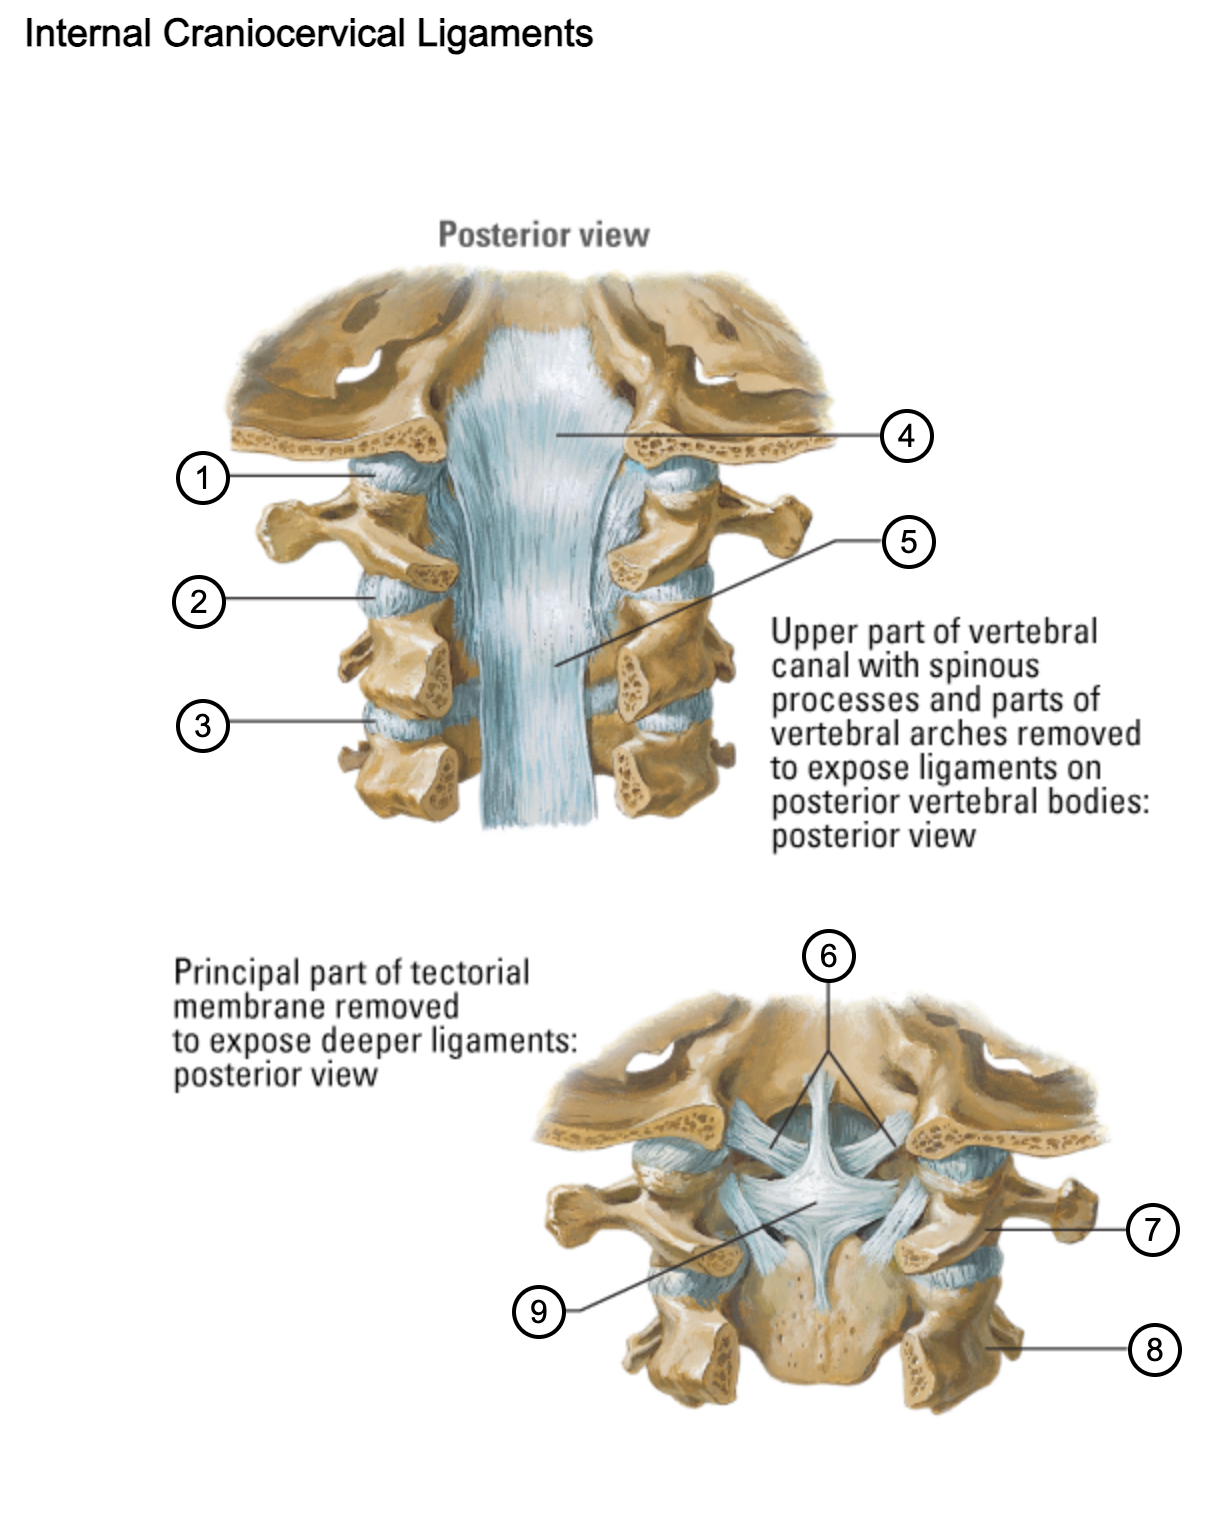

1

capsule of atlantooccipital joint

2

capsule of lateral atlantoaxial joint

3

capsule of zygapophysial joint (between axis and C3 vertebra)

4

tectorial membrane of cervical vertebral column

5

posterior longitudinal ligament

6

alar ligaments

7

atlas (C1)

8

axis (C2)

9

cruciform ligament (superior longitudinal band; transverse ligament of atlas; inferior longitudinal band)